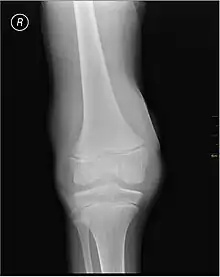

![]() | |

| Protein structure of coagulation factor VIII, of which its deficiency is the cause of haemophilia A. | |